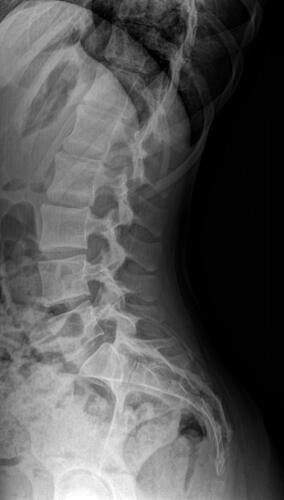

A Vá tem 13 anos e precisa urgentemente realizar uma cirurgia na coluna.Valentina foi surpreendida com o diagnóstico de escoliose hepática grave com 67 graus de desvio (desvio longitudinal da coluna), e precisa realizar com urgência a cirurgia corretiva, os exames foram realizados em Porto Alegre, mas a cirurgia está marcada para dia 13/07 em São Paulo devido a gravidade do caso, para isso a família terá que ficar residindo próximo ao hospital em São Paulo por no mínimo 30 dias para uma plena recuperação. Sabemos bem que qualquer procedimento cirúrgico é delicado, na coluna então nem se fala.Após o diagnóstico e o prognostico dessa doença a família se desfez de alguns bens (carro e moto) para cumprir os prazos dos exames e consultas, necessitando agora arrecadar o valor para a estadia da pequena Valentina e seu pós operatório (medicação, consultas e fisioterapia).

Em anexo os exames (laudo e imagens) para expressas a gravidade do caso.